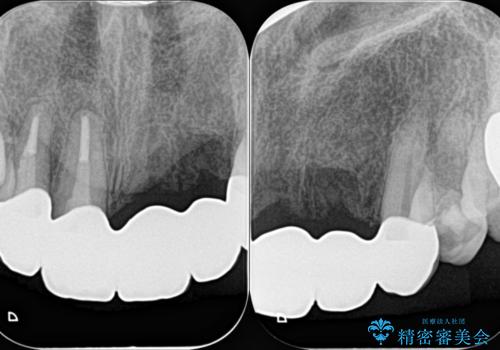

一見して問題ないように見える左側の2前歯は、セラミックを除去してみると亀裂や虫歯の再発が見られました。

抜歯時に可及的に歯肉のボリュームを保つよう骨充填材とコラーゲン製剤による填塞を行い審美的かつ機能的なブリッジとなるよう治療を進めます。

一件綺麗に見えるセラミックも適合や精度が悪いと、内部で虫歯が進行し亀裂や破折、悪臭の原因となることがあります。